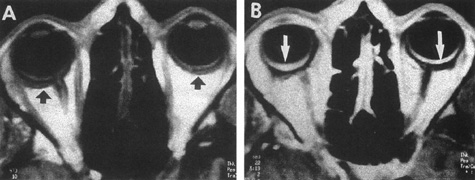

The detection of intracranial AVMs is facilitated by CT scanning and MRI (Fig. 10),88 but optimal management requires selective angiography89 that assesses the size and configuration of the mass, the number and location of feeding arteries, the flow characteristics and degree of steal from brain parenchyma, and the pattern of venous drainage.

Fig. 10. Neuroimaging of arteriovenous malformation. A: Coronal magnetic resonance imaging (MRI) (TR, 600 ms; TE, 20 ms) shows wedge-shaped vascular mass extending from the surface of the parietal cortex (white arrows) to the lateral ventricle (black arrows; asterisk, arterial feeder). B: Posteroanterior left arteriogram of the same lesion. C: Axial computed tomography scan with contrast enhancement. D: Axial MRI of a large arteriovenous malformation, first echo (TR, 2000 ms; TE, 20 ms). E: Second echo (TR, 2000 ms; TE, 90 ms). (From Smith HJ, Strother CM, Kikuchi Y, et al: MR imaging in the management of supratentorial intracranial AVMS. AJNR Am J Neuroradiol 9:225, 1988.)